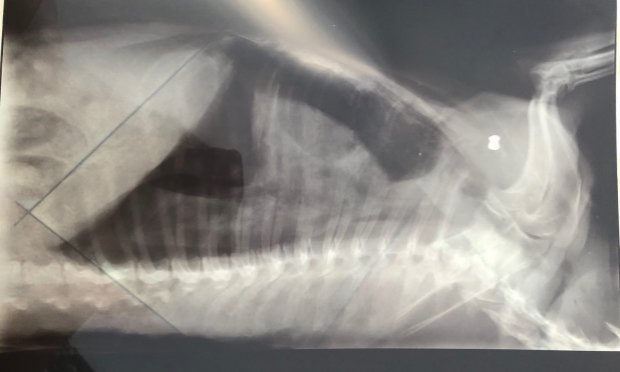

Radiographie de la balle qui a tué notre chienne

Voici une photo de la radiographie faite par notre vétérinaire. On y voit très distinctement l'impact du plomb côté droit du thorax.

Le plomb a provoqué un emphysème ainsi qu'une hémorragie pulmonaire responsable de la mort de Harper.